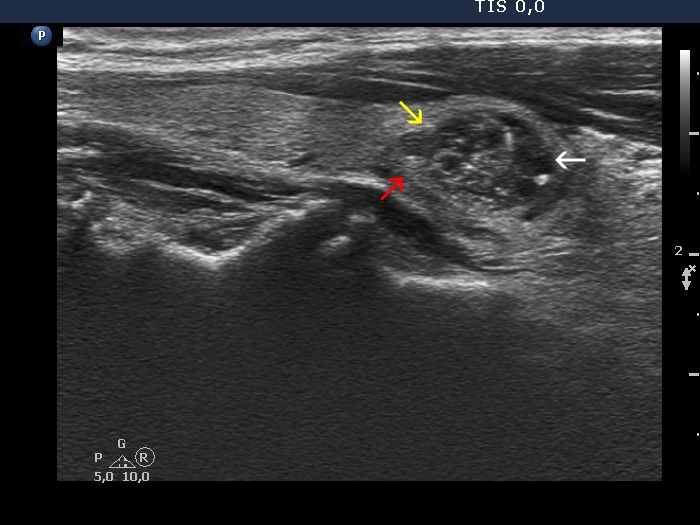

The echogenicity of the nodule - case 2166 (ultrasonographic picture 6b)

Right lobe, longitudinal view. The nodule has parts which show different echogenicities: white arrow points to a deeply hypoechoic, yellow does to a moderately hypoechoic portion of the nodule while an echonormal area of the lesion is signed with red arrow.